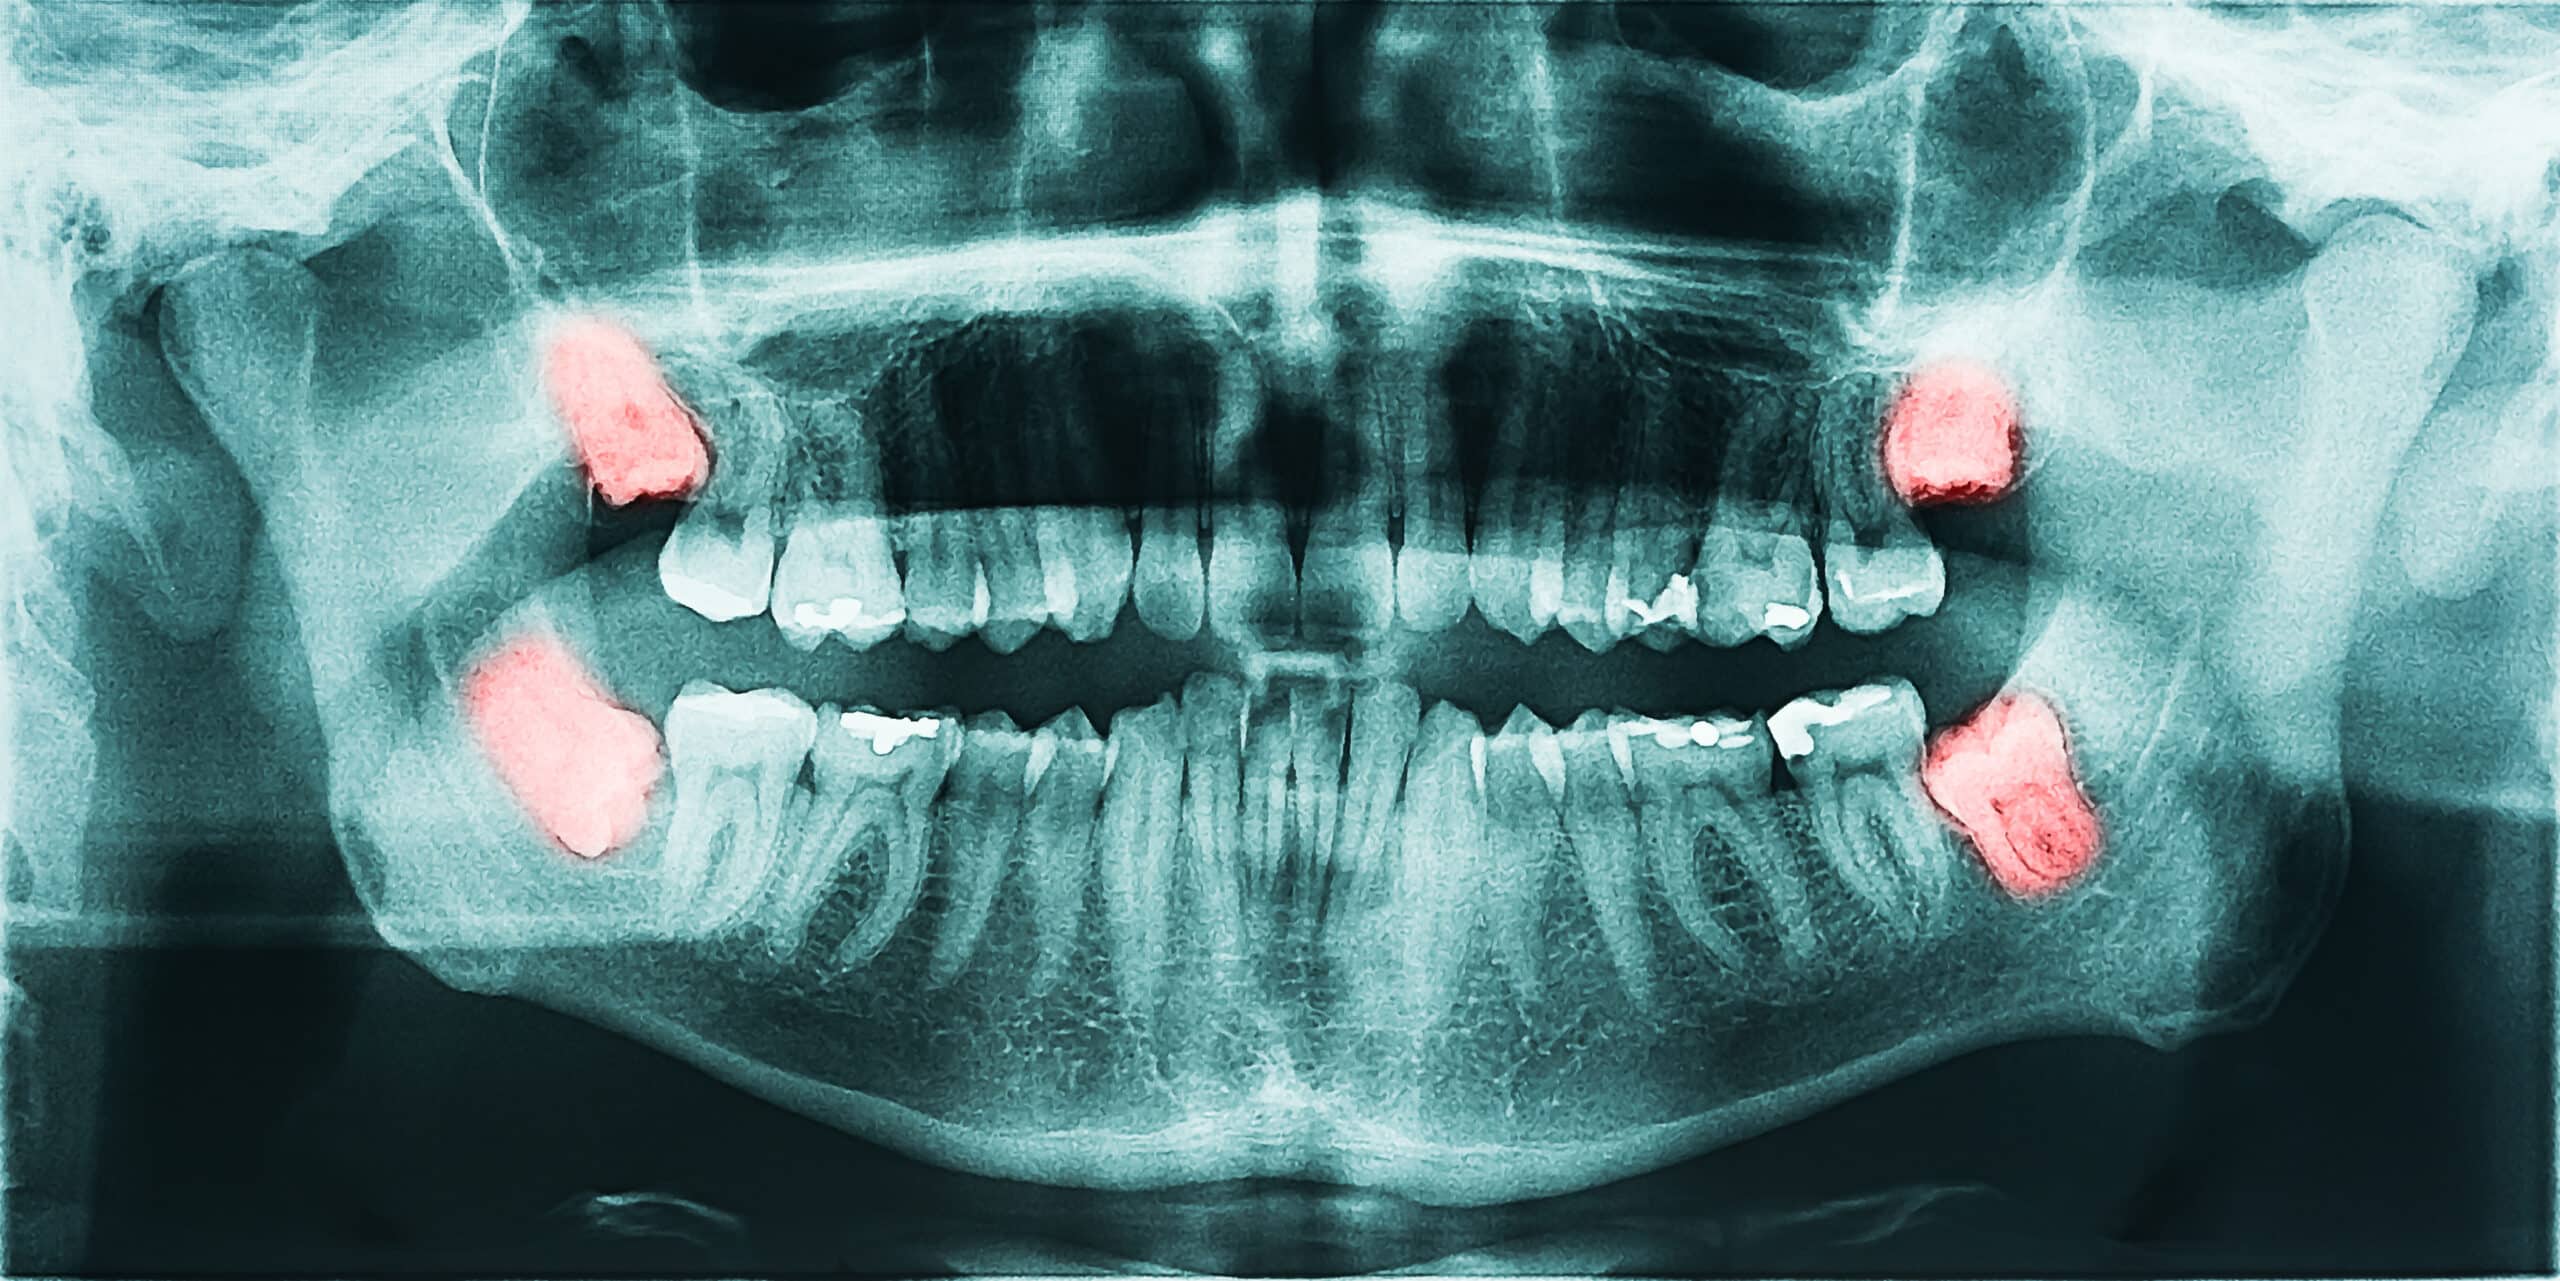

Wisdom teeth are simply your third set of molars. While some people have enough room for these teeth to grow in, most do not. Wisdom teeth can present a problem particularly due to their location in the mouth.

Often, they will need to be extracted if there is an inability to properly clean them, pain, or if there is not enough room for them. Most of the time, we recommend young adults remove their wisdom teeth sometime around their college years.

You may have asked yourself, “why do I need my wisdom teeth removed?” We are here to answer that question for you. Put simply, for most people there is not enough space in their mouths to allow these teeth to erupt and be in a position that makes them easily cleanable.

The back teeth that erupt prior to wisdom teeth block them out and preclude them from erupting because of the limited space. Sometimes, wisdom teeth will even be “partially erupted,” meaning that you can see some of the tooth in the mouth, but not all of it. These are particularly dangerous as they are virtually impossible to clean and can lead to infection.

In general, unless the wisdom teeth are in a position where you can easily keep them clean, we recommend removing them before problems occur.